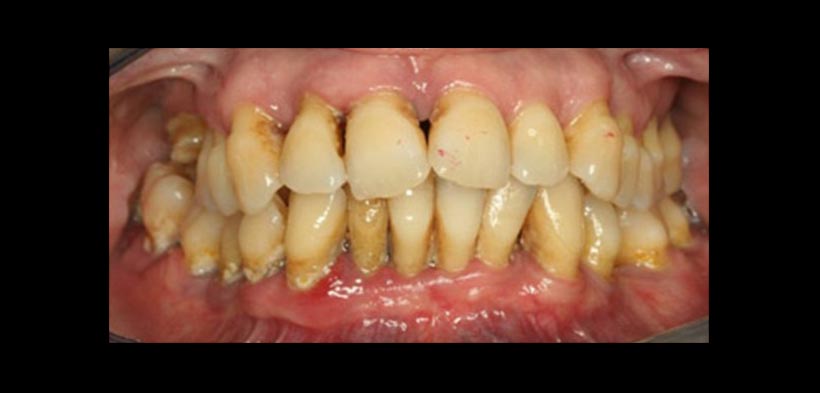

Figura1. Paciente que padece de periodontitis crónica, en la cual existen bolsas periodontales, recesión gingival y mineralización de la placa dental. Se evidencia la gingiva eritematosa muestra de una mayor vasculatura, existe una alta probabilidad de que las bacterias orales y sus productos metabólicos afectan directamente el endotelio mediante la estimulación de la formación de placas ateroscleróticas.